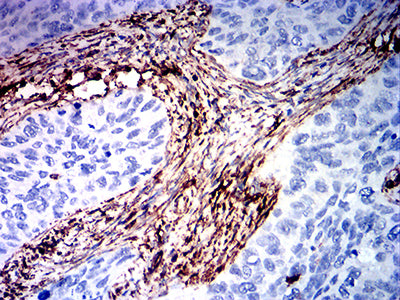

分类: 科研抗体货号: 31860别名: ACTSA;α-Smooth Muscle Actin;Alpha-actin-2;Alpha actin 2应用: WB,IHC,FCM反应种属: Human, Mouse, Rat

分类: 科研抗体货号: 31871别名: FLJ36605; VIM应用: WB,IHC,FCM反应种属: Human, Mouse, Rat